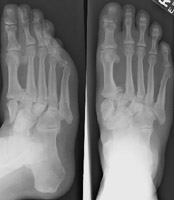

Charcot joint or neuropathic joint typically affects the ankle and tarsal joints due to diabetes. Tabes causes this phenomenon in the knees while syringomyelia leads to Charcot changes at the shoulder. This condition is characterized by the "six D's" of: (1) destruction, (2) density (increased), (3) disorganization, (4) dislocation, (5) distension (fluid), (6) debris. The typical appearance is that of severe hypertrophic changes and sclerosis due to ischemic necrosis.

- Click on the image for a larger versionAAP and oblique radiographs of the foot. In addition to the acute fracture of the proximal phalanx of digit one, these two images show the typical appearance of Charcot changes at the tarsometatarsal joints.